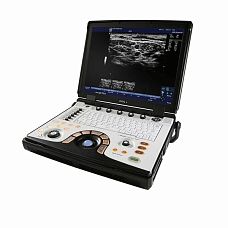

УЗИ аппарат Chison SonoTouch 80 Pro

Характеристики УЗИ аппарат Chison SonoTouch 80 Pro

Переносной ультразвуковой сканер Chison Sonotouch 80 Pro применим для различных сфер - акушерства, гинекологии, урологии, ангиологии, маммологии, кардиологии, ортопедии, педиатрии, неонатологии, ветеринарии, биопсии и т.д. Аппарат выполнен в форме ноутбука с весом до 5.5 кг. Эргономичная панель управления позволяет добраться практически до любой функции за одно нажатие и имеет функцию автоподстройки подсветки в зависимости от окружающего освещения. Sonotouch 80 Pro оснащен бесштырьковым портом для подключения легковесных ультразвуковых датчиков одним движением.

Технические характеристики УЗИ аппарат Chison SonoTouch 80 Pro